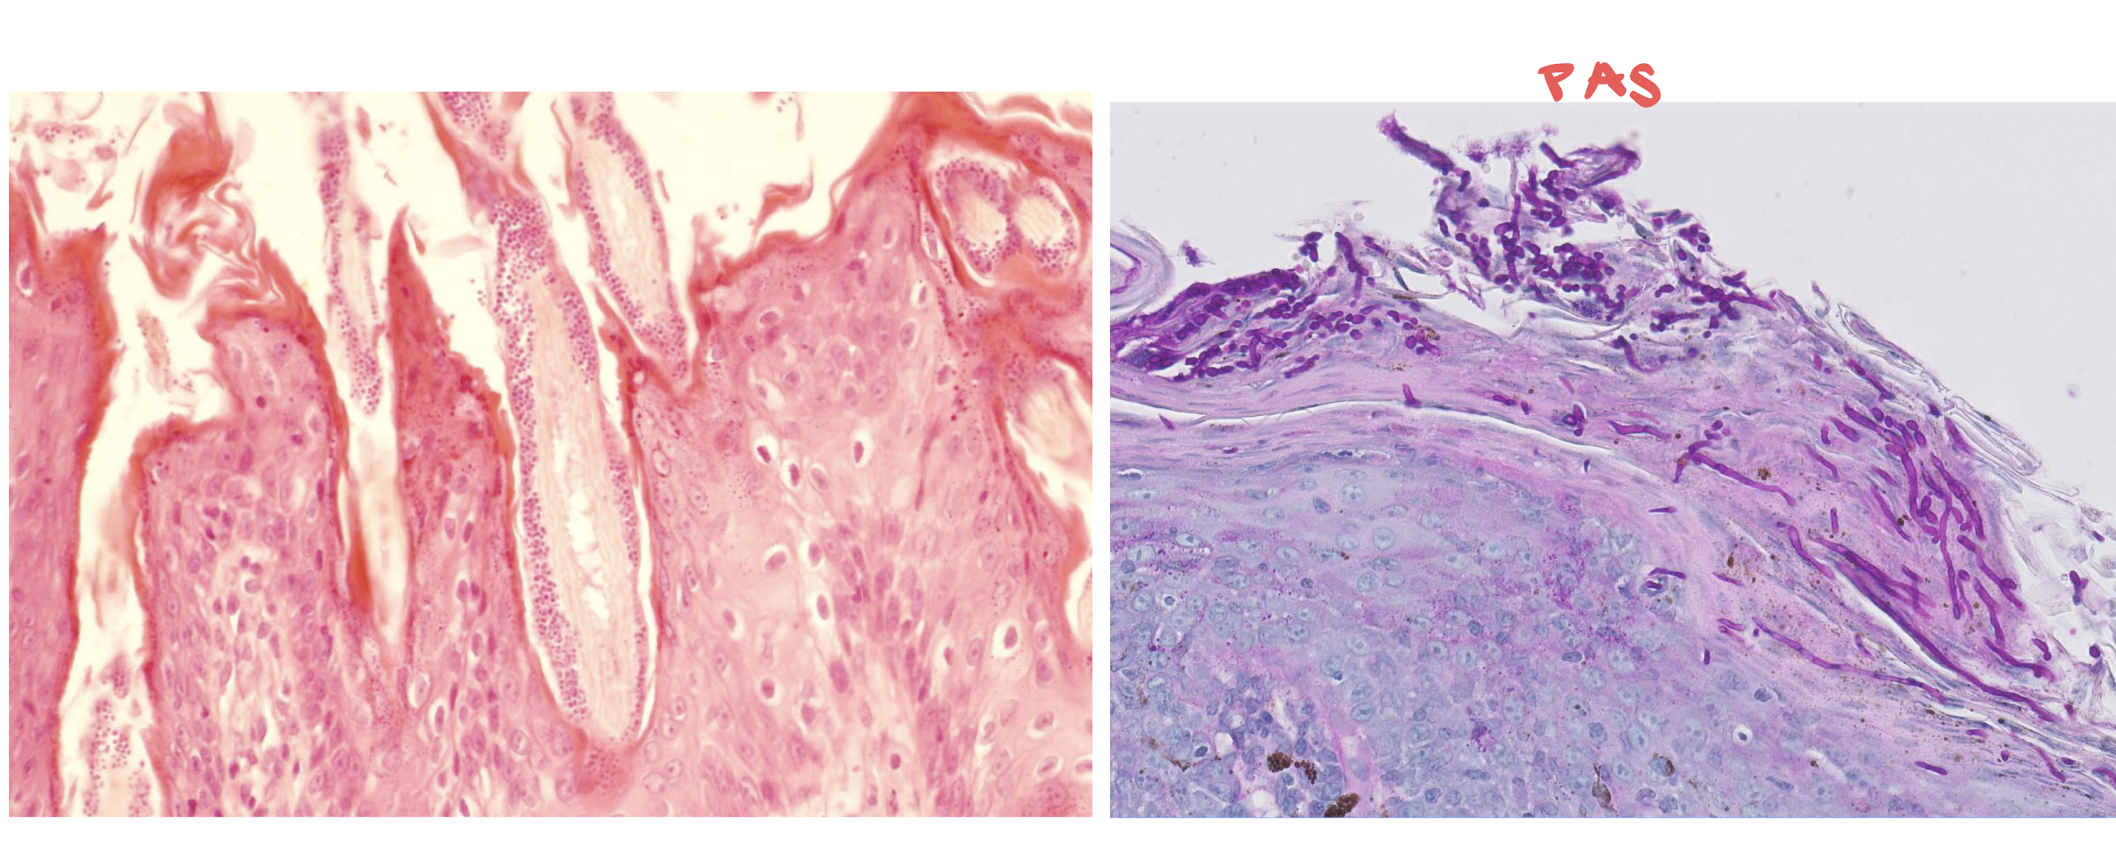

dermatophytosis (ringworm)

folliculitis!!

malassezia dermatitis